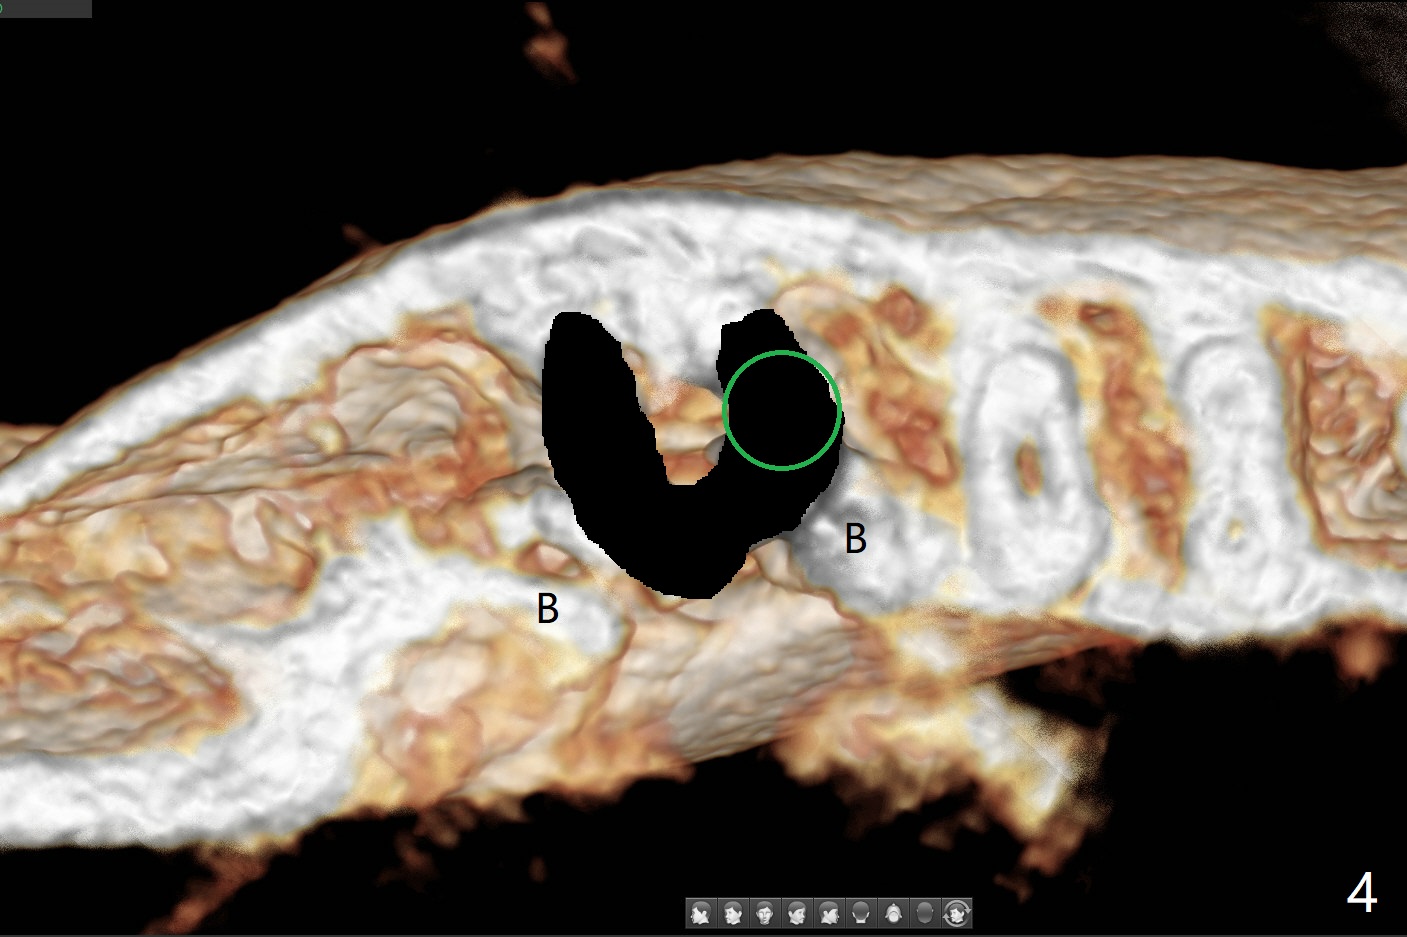

36岁女,右下第二磨牙颊侧瘘道,近中牙槽窝(图一:M)离下牙槽神经远,将是种植位点。图二是该牙CT3维横断面,显示近中(M),远中(D)牙根之间颊侧(L: 舌侧)连接(*);牙齿拔除后,牙槽窝成C型(图三,面对舌侧);由于颊侧骨板(图四:B)中断,缺损,植体将植入近中舌侧牙槽窝(绿色,导板)。优点便是三面骨质包绕(rao,图五),只有颊侧需要大量粘性骨粉(图六:*)。